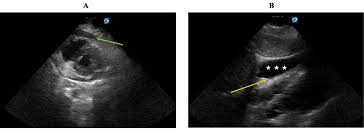

Pericardial effusion, the buildup of fluid in the pericardial sac surrounding the heart, can occur as a result of various medical conditions. In some cases, pericardial effusion may be a recurrent problem, which requires careful management to ensure the patient’s well-being. This article examines the case of a patient with delayed progression of melanoma who experienced recurrent pericardial effusion and explores the impact of immune checkpoint therapy on their treatment journey.

Pericardial effusion can be caused by multiple factors, such as inflammation, infection, malignancy, or autoimmune disorders. The accumulation of fluid in the pericardial sac puts pressure on the heart, compromising its ability to efficiently pump blood. This can lead to various symptoms, including chest pain, shortness of breath, and heart palpitations.

Treating pericardial effusion typically involves addressing the underlying cause and managing the fluid buildup. In certain situations, drainage of the accumulated fluid may be necessary to relieve symptoms and prevent further complications. However, in cases of recurrent pericardial effusion, there is often a need for a more targeted approach.

Mr. Johnson, a 52-year-old male, was diagnosed with stage III melanoma six years ago. Despite undergoing surgery and targeted therapy, he experienced recurring episodes of pericardial effusion over the past year. Each time, the fluid was drained, providing temporary relief. However, Mr. Johnson’s oncologist noticed an interesting pattern – the occurrences of pericardial effusion seemed to coincide with a halt in tumor progression.

Opting for a closer examination, the medical team analyzed Mr. Johnson’s case in detail. They discovered that whenever his melanoma reached a stable state, the immune checkpoint therapy he received seemed to have a profound impact on his pericardial effusion. The therapy, by boosting the immune system’s ability to recognize and attack cancer cells, potentially played a key role in preventing the progression of both the melanoma and the pericardial effusion.